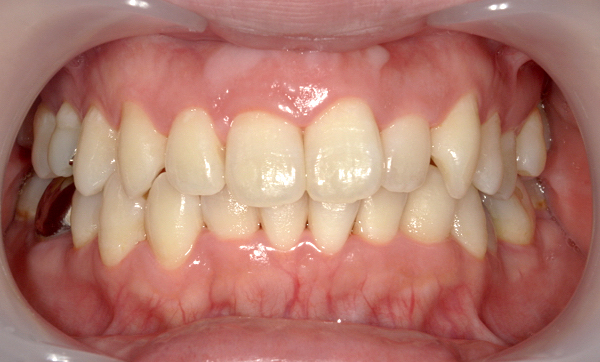

症例_009 「上下の前歯」症例

治療期間:7ヶ月金額:54万円+税20代女性捻転歯一部の反対咬合前歯のガタガタ

Before | After |